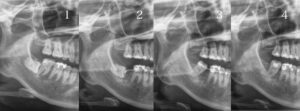

バイマックスでの本当の矯正治療によるくちもとの変化